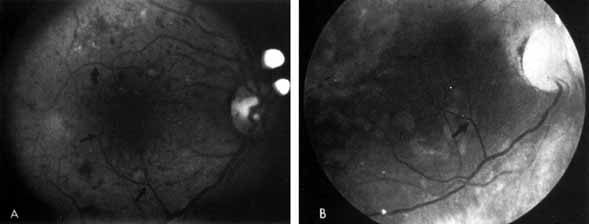

Fig. 19 A. Neovascularization immediately after xenon-arc photocoagulation. B. One year later. The neovascularization elsewhere (NVE) has been obliterated.

To prevent new areas of neovascularization, several ophthalmologists began to photocoagulate not only neovascularization but all intraretinal hemorrhages as well (“shoot the red”), on the grounds that they represented areas of hypoxia that could later develop into proliferative retinopathy. They soon noted that the cases that had the most intraretinal hemorrhages and therefore received the most initial photocoagulation frequently had the best long-term results, with permanent regression of neovascularization (Fig. 20). In such cases, the optic disc often became pale, indicating optic atrophy.

Fig. 20 A. Neovascularization of the disc (NVD) and a small vitreous hemorrhage. Panretinal photocoagulation was given. B. Two months later, the NVD has completely regressed.

At about the same time, Aiello and co-workers,132,133 and others134–137 noted that patients with unilateral high myopia, extensive chorioretinal scarring, glaucoma, and optic nerve atrophy frequently had markedly asymmetrical retinopathy. The prior retinal or optic nerve damage seemed to protect that eye from diabetic retinopathy (Fig. 21). These investigators initiated the concept of PRP (Fig. 22). They theorized that photocoagulation burns scattered throughout the retina would decrease the retina's need for oxygen and thereby prevent neovascularization from developing or might even cause regression of existent neovascularization. Early studies showing the benefits of PRP were criticized on statistical and other grounds and were not widely accepted.138,139

Fig. 21 A. Right eye of a patient with neovascularization of the disc (NVD), numerous retinal hemorrhages, soft and hard exudates. B. Left eye of the same patient. Note pale optic disc from previous ischemic optic neuropathy and minimal diabetic retinopathy.

It remained for a national collaborative study initiated by Davis and sponsored by the National Institutes of Health (The Diabetic Retinopathy Study (DRS)) to prove that both xenon-arc and argon-laser PRP significantly decrease the likelihood that an eye with high-risk characteristics will progress to severe visual loss.140–142 High-risk characteristics are defined as eyes with (1) NVD greater than one-fourth to one-third disc area, (2) any NVD and vitreous hemorrhage, or (3) NVE greater than one-half disc area and vitreous or preretinal hemorrhage (see Fig. 20). The main findings of the DRS are summarized in Table 1.